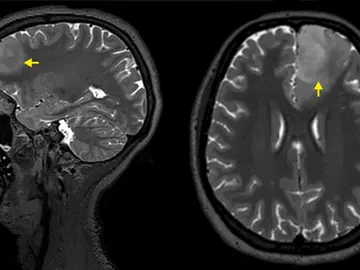

El uso de este anticonceptivo podría provocar un tumor cerebral

Descubren una nueva terapia contra el gioblastoma

Este fármaco sería efectivo contra los tumores cerebrales

Descubren dos genes esenciales relacionados con la reducción de tumores cerebrales